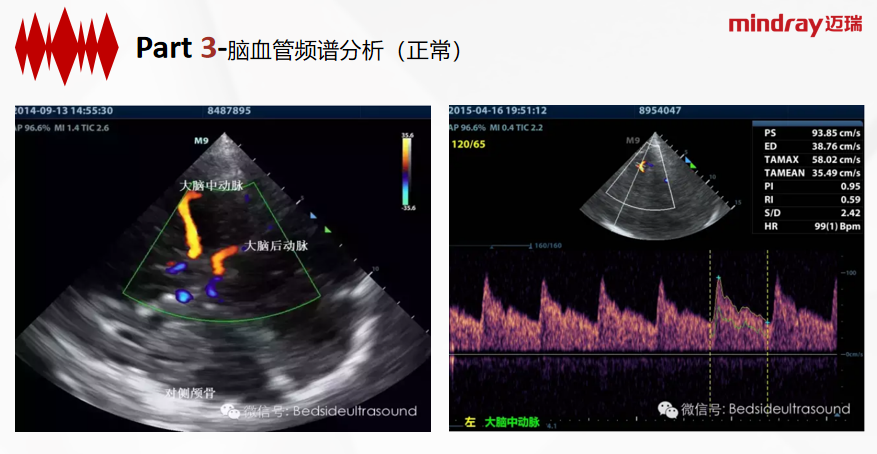

TCCD(Transcranial color-coded duplex sonography)经颅彩色多普勒超声检测技术,是一种常用的脑血管疾病影像学检查技术。

TCCD与TCD区别:成像基础上,加入二维灰阶成像及彩色多普勒血流成像,可直观地识别颅内结构,更准确地定位颅内血管,通过角度校正,可更为准确地取得狭窄处及狭窄前、后血管腔的实时血流动力学信息。